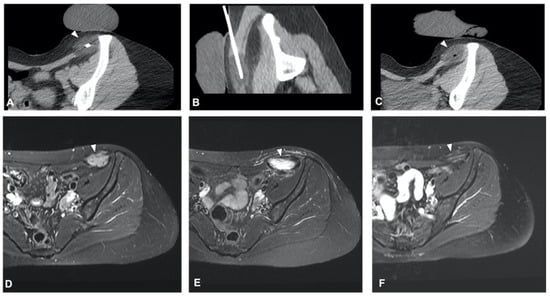

2.2. Sacrococcygeal Tumors and Chordoma

- Li, L.; Jiang, X.-F.; Sun, L.-J.; Fu, Y.-F.; Zhang, W. Computed tomography-guided argon-helium cryoablation for sacrum chordoma. Medicine 2020, 99, e22604. [Google Scholar] [CrossRef]

- Kurup, A.N.; Woodrum, D.A.; Morris, J.M.; Atwell, T.D.; Schmit, G.D.; Welch, T.J.; Yaszemski, M.J.; Callstrom, M.R. Cryoablation of Recurrent Sacrococcygeal Tumors. J. Vasc. Interv. Radiol. 2012, 23, 1070–1075. [Google Scholar] [CrossRef]